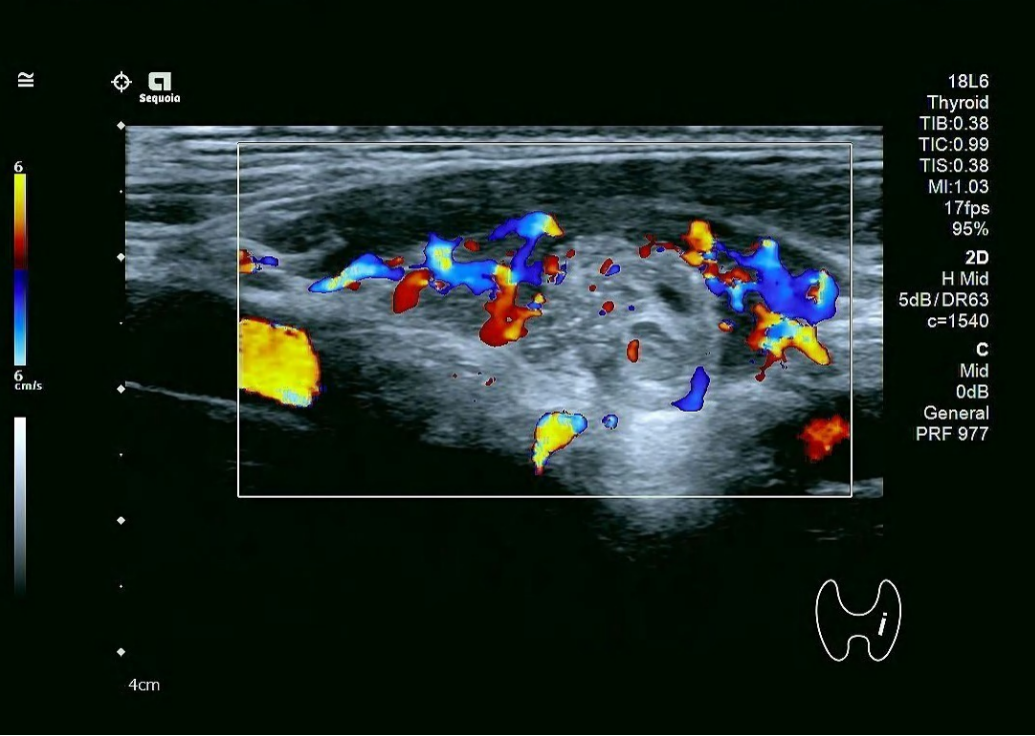

甲状腺彩超:甲状腺双侧叶增大并弥漫性声像图改变、血流稍丰富,甲状腺右侧叶结节(C-TIRADS 4A类),甲状腺峡部结节(C-TIRADS 3类)。

甲状腺彩超